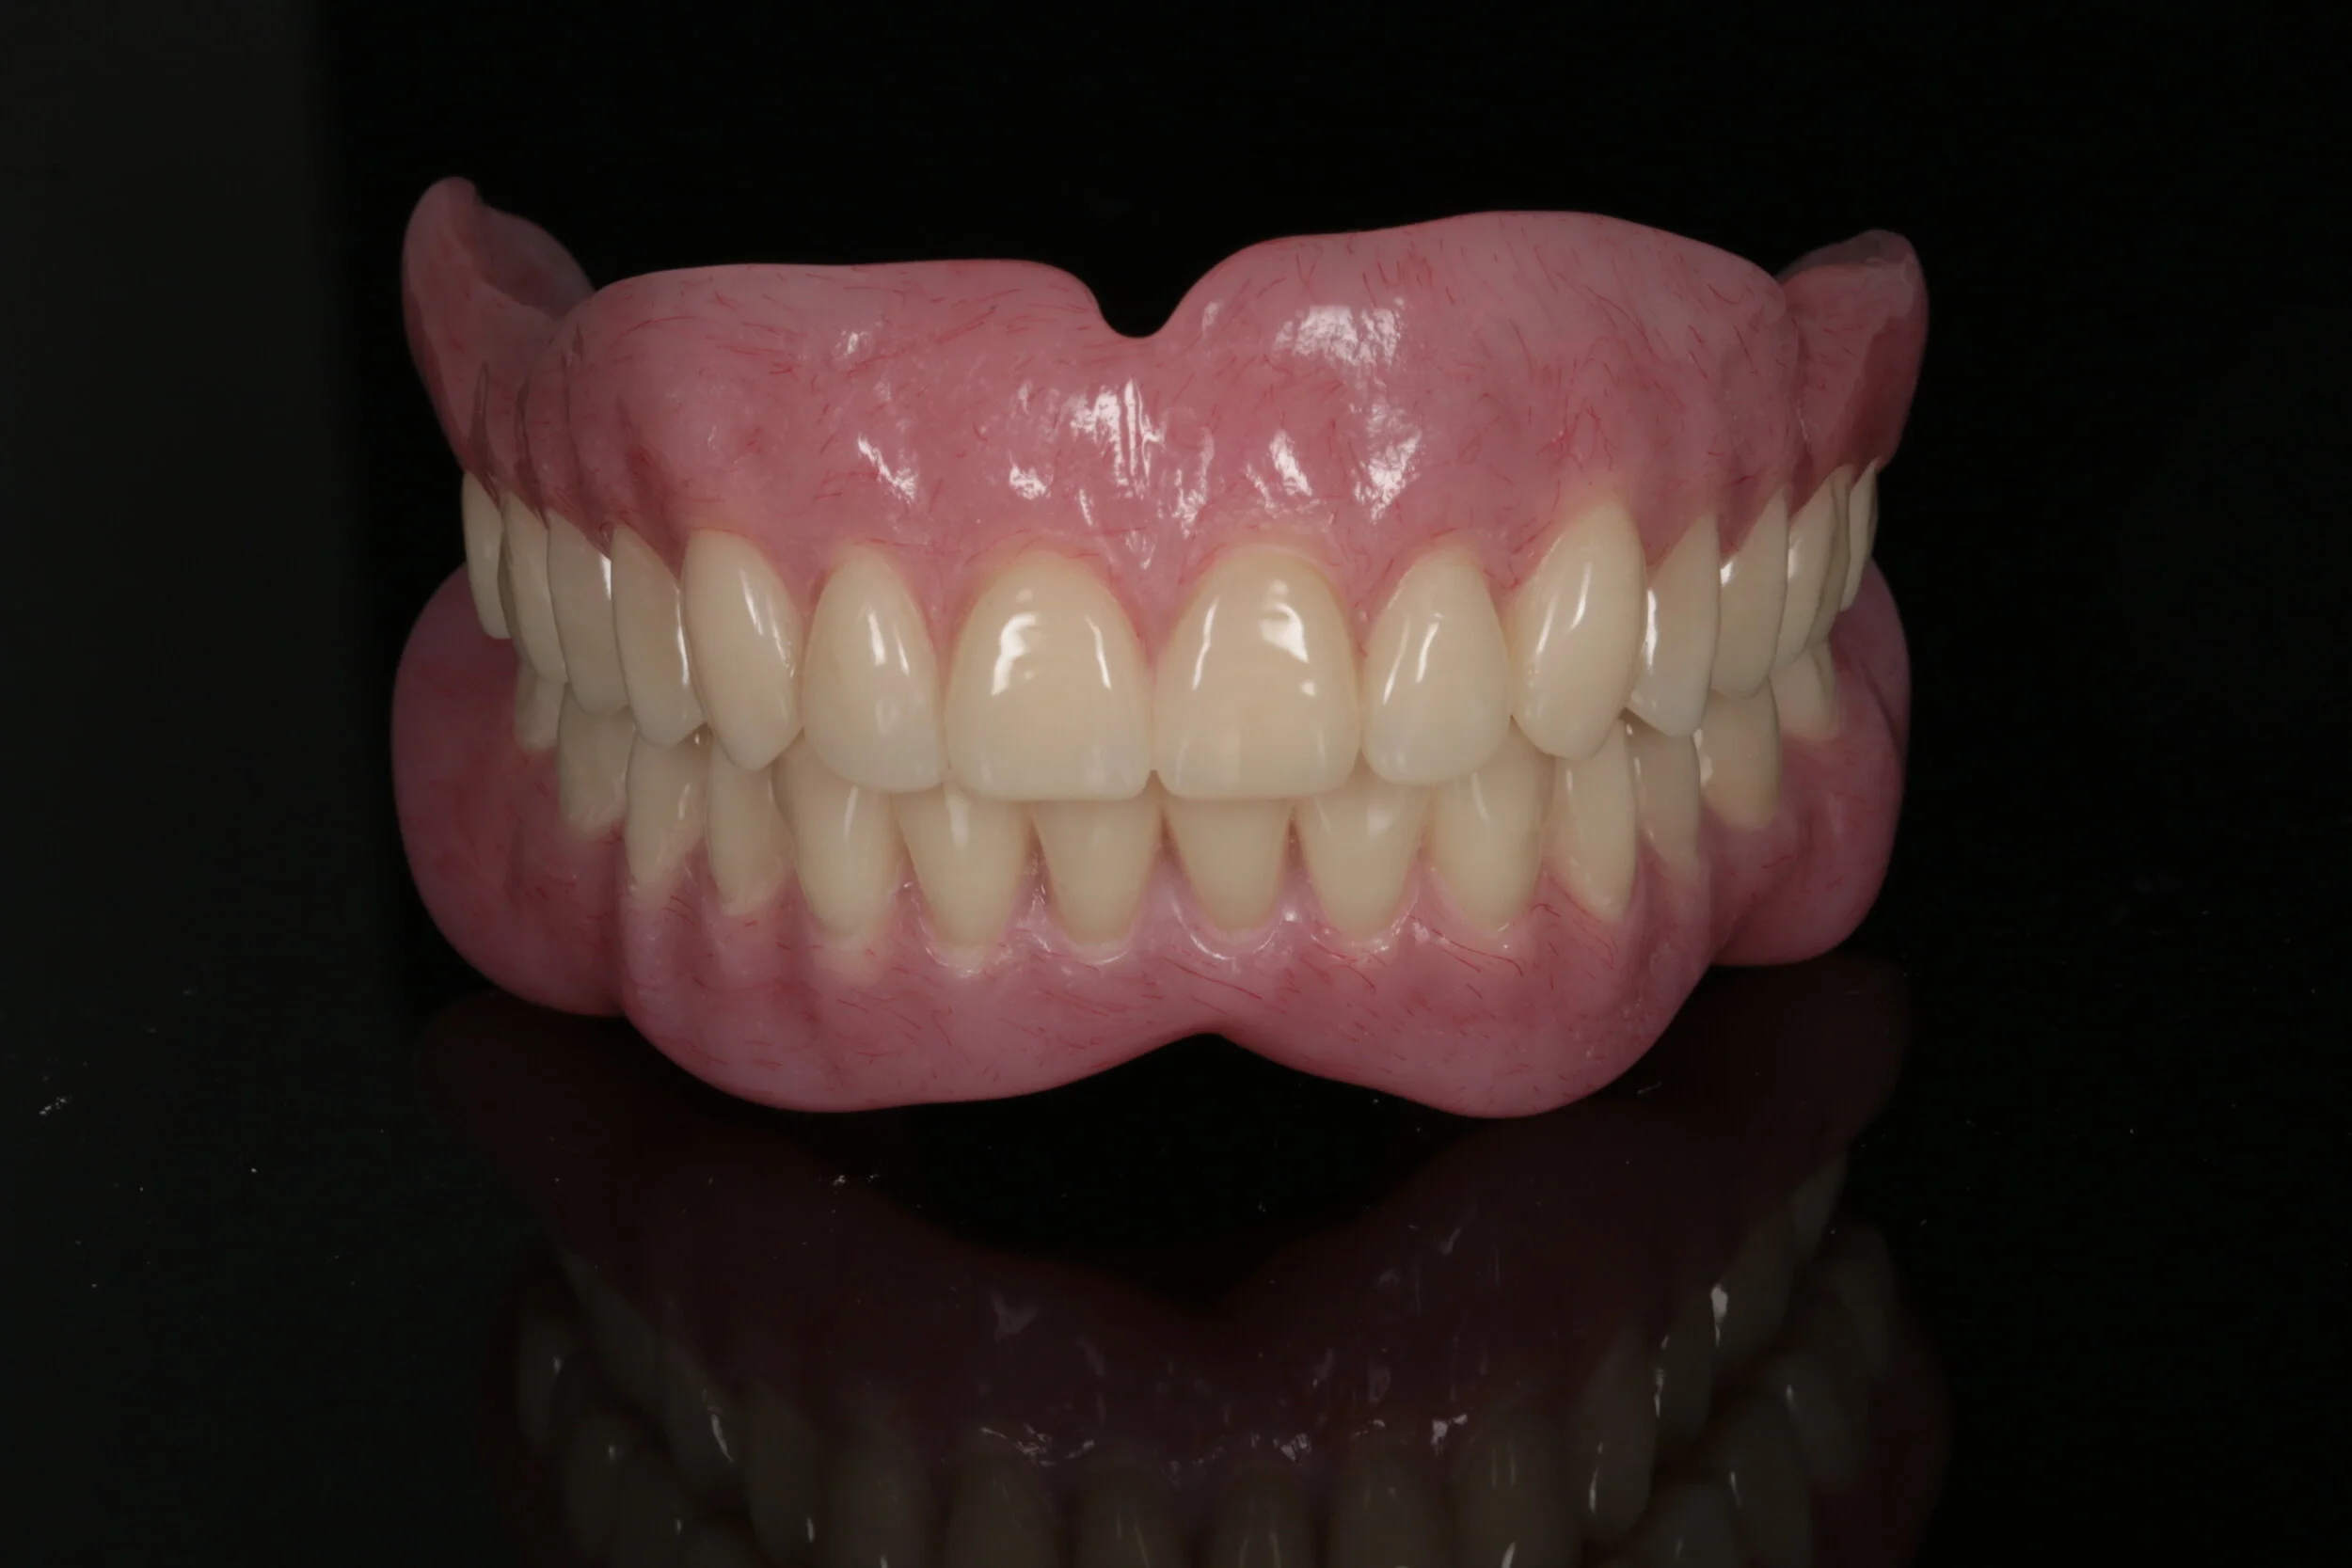

Course Outline

Dentists are seeing an increase in patient edentulism in their practices. A well-designed partial removable dental prosthesis of high quality improves patients’ smiles, chewing and speech function. This treatment modality is often a valid alternative to fixed dental prostheses supported by teeth or implants. In many complete edentulous scenarios, a removable denture stabilised and retained by implants is a preferred outcome compared with implant fixed prostheses. Diagnosis, planning decisions, treatment procedures and clear maintenance protocols are the keys to success in removable prosthodontics.

This course will help you develop your clinical skills in restorative dentistry so you can diagnose, plan, deliver, and maintain removable tooth, mucosal, and implant borne prostheses to enable you to treat a variety of patients who visit your practice.